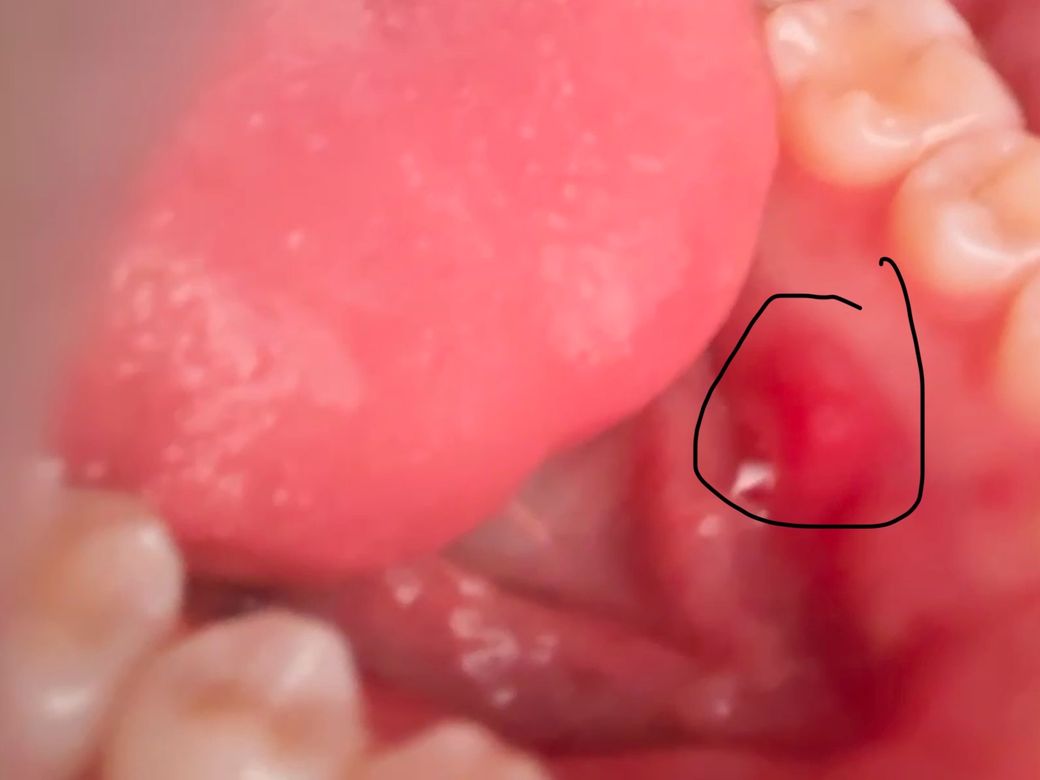

이거 구강암인가요 구내염인가요..?

아까 밥 먹고 혀에 살짝 부은 느낌이 나서 거울을 봤는데 이렇더라고요 이거 구강암인가요..? 혀에 닿으면 살짝 아프긴 합니다ㅠㅠㅠ

구내염인거 같으니 최대한 자극이 가지 않도록 하시거나 약국에서 구내염 약을 구매 하셔서 바르시면될것같습니다.

사진으로만 봤을 경우에는 잇몸에 외부 자극으로 인해서 상처가 난 것으로 보입니다. 구강 점막 조직은 잘 아무는 조직이기 때문에 보통 이 주 정도가 지나면 해당 부위가 괜찮아지게 됩니다. 불편한 부위가 자극이 되지 않도록 관리를 해주는 것이었으며 불편감이 크다면 오라메디와 같은 구강 점막 연구를 사용해보는 것을 권유드립니다.

사진상으로 봤을때 특별히 악성병소의 양상은 아니니 너무 걱정은 안하셔도 됩니다 구강내과가서 체크해보시기 바랍니다